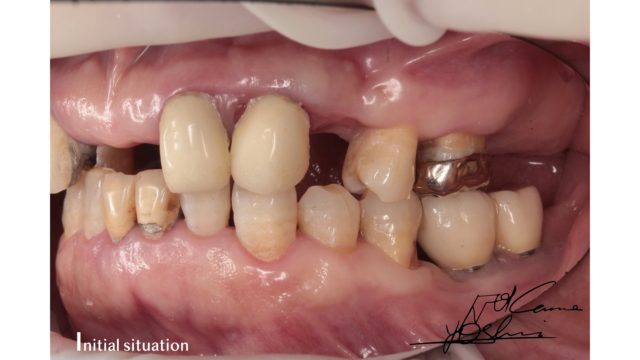

お口の右側、BEFORE写真です。

お口の右側、AFTER写真です。